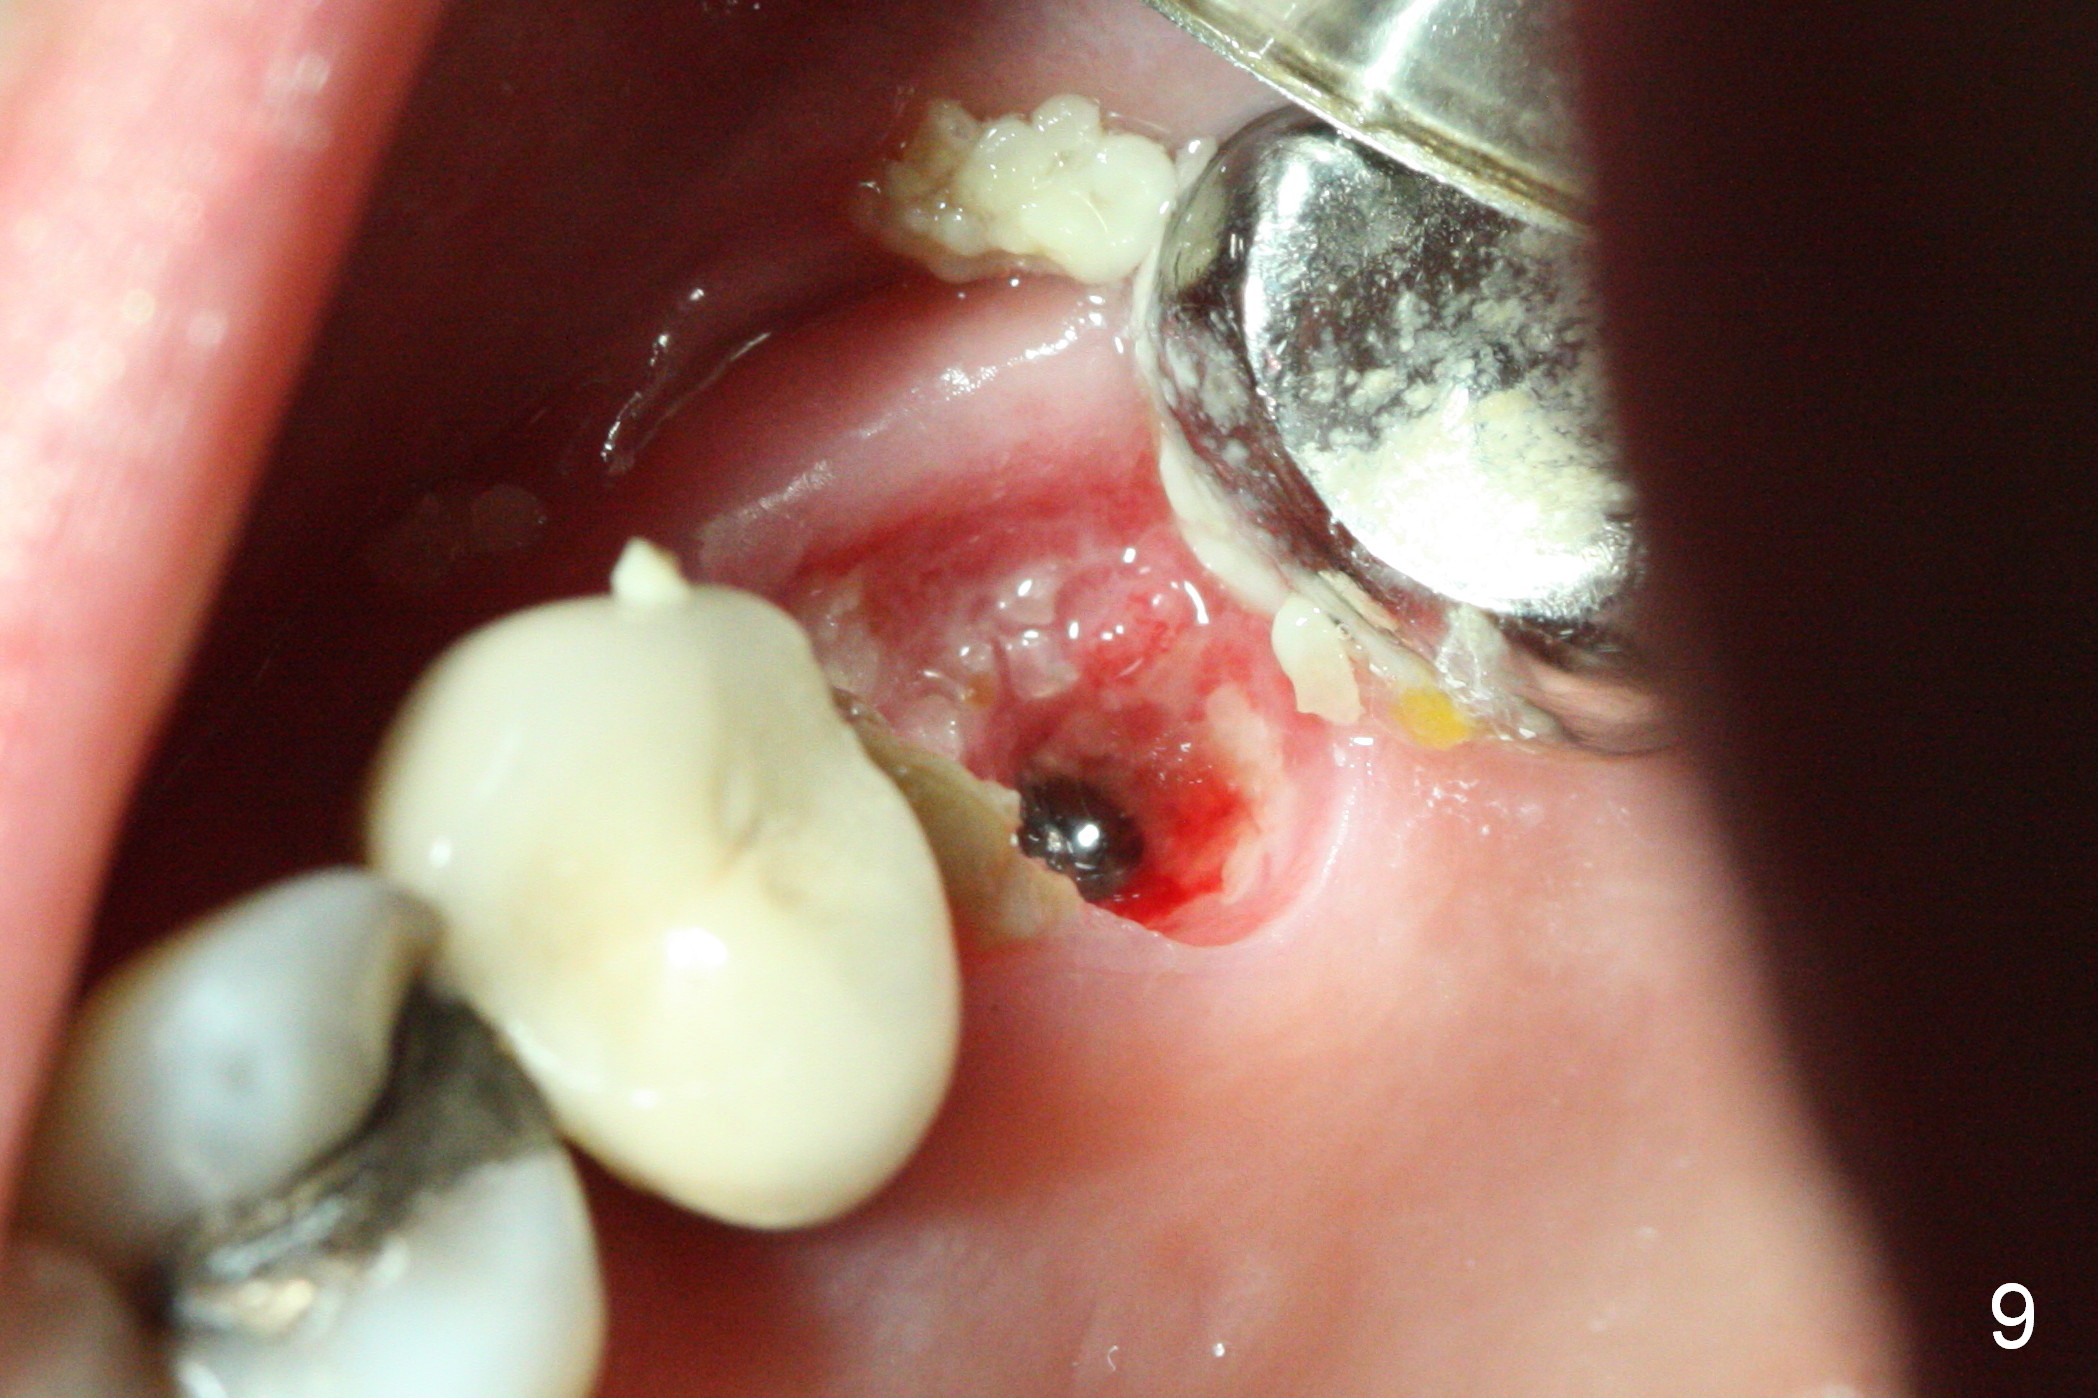

The patient is doing well 9 days postop.  The immediate provisional is loose and over-sized.  It is removed for trimming and reline; the socket and bone graft (Fig.8 *) are healing.  It appears that an angled abutment is required next time of provisional revision.  When an angled abutment is being placed 23 days postop (Fig.9), it appears to wiggle the implant due to its long leverage.  Instead a healing abutment is placed.  The implant is unstable 4.5 months postop with seemingly excessive bone-implant gap (Fig.10 <).  The 5.5x9 mm implant is removed.  A 5x17 mm tap is used to change the trajectory and sinus lift, followed by 6x17 one (Fig.11).  Finally a 6x14 mm tissue-level implant is placed with insertion torque > 50 Ncm (Fig.12; vs. <20 Ncm (Fig.7,10)) and improved trajectory.  An immediate provisional is fabricated to prevent the mesial drifting of the tooth #15 (Fig.13 P (*: occlusal clearance)).  By using the taps and placing the longer implant, the sinus lift is more obvious (compare Fig.10 and 12 (*)).  Sinus lift remains evident 3.5 months postop (Fig.14) with apparently osteointegration (Fig.15).